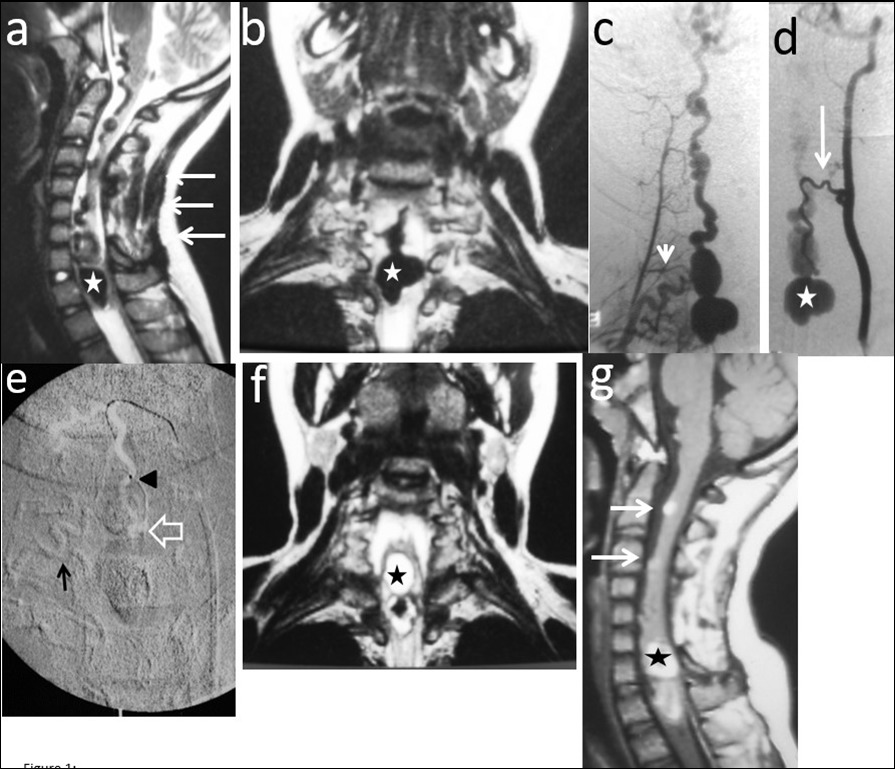

Figure 1.Case # 1: a) T2W sagittal and b) coronal MRI images showing a large bilobed varix in the anterior aspect of the spinal cord at the vertebral levels of C7 and T1 (star). Notice the large venous drainage ascending ventrally from the cervical spinal cord towards the brainstem (thin arrow). A previously C3 to C7 “decompressive” laminectomy was performed (arrows). c) Right thyrocervical trunk demonstrates that the main feeder to the fistula is the right artery of the cervical cord enlargement (short arrow). d) Another feeder from the ASA, branch of the left vertebral artery is visualized (thin arrow). The venous varix is shown (star). e) Roadmap image at the time of micro catheterization of the left ASA. The tip of the microcatheter (arrowhead) was further advanced to the fistulous site (open arrow) and 0.8 cc of 90% n-bca in lipiodol was injected. Also notice the glue cast injected in the artery of the cervical enlargement (thin arrow). f) MRI T2W FLAIR coronal and g) sagittal (postoperative day 5) showing fresh clot in the venous varix (star) with retrograde thrombosis of the ascending draining veins (arrows). The MR signal of the spinal cord remained normal.

Two out of 4 patients were diagnosed and studied preoperatively with both spinal MRI and CT scans, 1 patient with MRI and the other patient with CT/CT Angiography with 3D reconstruction. Large and tortuous flow voids with large to giant venous pouches or pseudoaneurysms (3 of our cases - type c) causing compression of the spinal cord were found lying ventrally and, in another one, posterolaterally to the spinal cord. Hyperintensity in T2W sequences in the spinal cord was noted in all of them. There were no cases where a hemorrhage was exhibited. The angiographic studies confirmed the 4 large or giant pouches at the draining vein fed by ASA and or PSA and ascending (2 cases), descending (1 case) or metameric (1 case) venous drainage. The blood flow was moderate in 1 case and very fast in the other 3 patients (see Table 2 and Figure 1, Figure 2, Figure 3, Figure 4).

We used transarterial approach and a single session achieving complete obliteration of the fistulae while preserving the normal vasculature, mainly the ASA, in all of our 4 cases using either different concentrations of n-bca alone tailored to the blood flow velocity (cases 1,2 and 3), or a combination of coils and onyx 18 (case 4). In this last case, the high flow fistula and the presence of a giant pseudoaneurysm at the venous varix compressing the spinal cord prompted us to deploy coils in the sac and in the draining vein to slow down the blood flow and decrease the chance of distal embolism. To date, we do not have Onyx of higher concentration than Onyx18 available in our country. In high flow macrofistulae, our strategy to slow down the flow to allow casting of the polymerizing embolic mixture in the fistulous site avoiding distal embolism includes lowering mean arterial pressure down to 60-70 mm Hg pharmacologically, by embolizing with concentrations of 66% of n-bca in lipiodol, as well as the placement of detachable coils in the event of very high flow with pseudoaneurysms at or very close to the fistulous site as a first step, to trap the liquid embolic material injected as second step (see Figure 1, Figure 2, Figure 3, Figure 4).